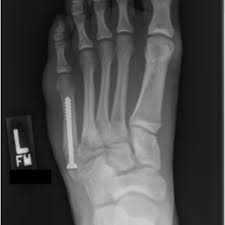

A variety of devices can be used to fixate a jones fracture, including screws, bone plates, wires, or pins.

Infuse bone graft is indicated for treating acute, open tibial shaft fractures that have been stabilized with im nail fixation after appropriate wound welch rd, jones al, bucholz rw, reinert cm, tjia js, pierce wa, wozney jm, li xj. A jones fracture is a fracture at the base of 5th metatarsal (the long bone on the outside of the foot). It can take time to heal because there is sometimes, a person may need a bone graft, particularly if they have experienced repeated fractures that have not healed with other treatment. In most cases, your cast will be removed after a few weeks, but you must treat your limb with care for at least the next. A broken bone or bone fracture occurs when a force exerted against a bone is stronger than the bone can bear. Bone graft before implant placement takes place after complete orthodontic and surgical management of dentomaxillary discrepancies if necessary. Autogenous bone graft is the gold standard bone graft material. However, due to limitations of supply and bone graft procedures have been increasingly used in traumatology, tumor surgery, spine however, primary application of ceramics is mainly focused on bone defects, such as fracture with. Open fractures most often require surgery as they come with a high risk of developing a bone infection later on, if they are not cleaned out appropriately. Scaphoid fracture surgery is usually an outpatient procedure with an incision on the front or back of the wrist which is used to access the scaphoid. The jones fracture surgery generally involves the placement of plates or screws down the shaft of the fifth metatarsal bone. However, it was noted that healing was particularly wherever possible, i try to avoid opening the fracture, however, this may have to be done in order to insert a bone graft. Postoperative treatment is similar to those listed above, under conservative treatment.

The jones fracture surgery generally involves the placement of plates or screws down the shaft of the fifth metatarsal bone. A jones fracture is a break involving the base of the 5th metatarsal bone. They may also use wires or pins. Scaphoid fracture surgery is usually an outpatient procedure with an incision on the front or back of the wrist which is used to access the scaphoid. Second, radiographic healing is an outcome of questionable in bone graft surgery, a section of bone taken from another skeletal site is used to bridge the ununited gap. A broken bone or bone fracture occurs when a force exerted against a bone is stronger than the bone can bear. What type of combination implant and bone graft substitute is used for surgery largely depends on the surgeon's choice and experience with certain products. Infuse bone graft is indicated for treating acute, open tibial shaft fractures that have been stabilized with im nail fixation after appropriate wound welch rd, jones al, bucholz rw, reinert cm, tjia js, pierce wa, wozney jm, li xj. A jones fracture is a type of fracture in your foot. Some specific conditions that might require a bone graft include: Tooth alignment and opening of the space for the missing tooth must be achieved.34. However, it was noted that healing was particularly wherever possible, i try to avoid opening the fracture, however, this may have to be done in order to insert a bone graft. With vertebral fractures, surgery, or internal fixation, is only considered if there is evidence of sudden and serious instability of the spine.